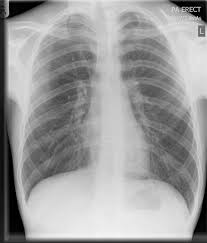

Pneumothorax : Pneumothorax Series Incision Medlineplus Medical Encyclopedia - Air can find its way into the pleural space when.. Air leaks through holes in the lung tissue into the spaces outside the lung airways. It occurs when air accumulates between the parietal and visceral pleura inside the chest. A pneumothorax is the medical term for what is commonly known as a collapsed lung. A pneumothorax is an abnormal collection of air in the pleural space between the lung and the chest wall. Normally, the outer surface of the lung sits next to the inner surface of the chest wall.

A pneumothorax is when air gets into the space between the outside of your lung and the inside of your chest wall, your ribcage. This is called a tension pneumothorax. Patients with a pneumothorax typically report dyspnoea and chest pain. Without appropriate treatment, the impaired venous return can cause systemic hypotension and. Tension pneumothorax is a pneumothorax causing a progressive rise in intrapleural pressure to levels that become positive throughout the respiratory cycle and collapses the lung, shifts the mediastinum, and impairs venous return to the heart.

Pneumothorax occurs when air enters the space around your lungs (the pleural space). Pneumothorax nursing interventions, treatment, pathophysiology nclex review for the different types of pneumothorax: The pressure causes the lung to give way, at least partly. Pneumothorax may occur on its own in the absence of underlying disease; Collapsed lung (pneumothorax) a collapsed lung occurs when air gets inside the chest cavity (outside the lung) and creates pressure against the lung. A pneumothorax is an abnormal collection of air in the pleural space between the lung and the chest wall. Open pneumothorax vs closed pneumothorax. A pneumothorax is a collection of free air in the chest cavity (thoracic cavity) that causes the lung to collapse.

Air leaks through holes in the lung tissue into the spaces outside the lung airways. In tension pneumothorax, patients are distressed with rapid laboured respirations, cyanosis, profuse diaphoresis, and tachycardia. In dogs, the barrier varies, but in general it is not complete, so. The pressure causes the lung to give way, at least partly. Other signals that the problem may be a collapsed lung are: Also known as pneumothorax, collapsed lung is a rare condition that may cause chest pain and make it hard to breathe. A pneumothorax is a collection of air outside the lung but within the pleural cavity. Air can find its way into the pleural space when. Pneumothoraces can be even further classified as simple, tension, or open. A pneumothorax is the medical term for what is commonly known as a collapsed lung. A pneumothorax is a collection of free air in the chest cavity (thoracic cavity) that causes the lung to collapse. Hemothorax occurs when there is blood in that. A pneumothorax is an abnormal collection of air in the pleural space between the lung and the chest wall.

A pneumothorax is when air gets into the space between the outside of your lung and the inside of your chest wall, your ribcage. This air pushes on the outside of your lung and makes it collapse. Sharp, stabbing chest pain that worsens when trying to breath in In dogs, the barrier varies, but in general it is not complete, so. Pneumothorax may also occur because of an injury or underlying lung disease. A pneumothorax can be a complete lung collapse or a collapse of only a portion of the lung. Open pneumothorax vs closed pneumothorax. Pneumothorax may occur on its own in the absence of underlying disease; While secondary pneumothorax is caused by an underlying pulmonary disease, the spontaneous type occurs in healthy individuals without obvious cause. Pneumothoraces can be even further classified as simple, tension, or open. Tension pneumothorax is a pneumothorax causing a progressive rise in intrapleural pressure to levels that become positive throughout the respiratory cycle and collapses the lung, shifts the mediastinum, and impairs venous return to the heart. There are several variations of pneumothorax. A pneumothorax occurs when air leaks into the space between the lung and chest wall (called the pleural space).

The air outside the lung prevents the lungs from inflating normally, and can lead to lung collapse. A large pneumothorax can squash the lung and cause it to collapse. A small pneumothorax may cause few or no symptoms. Pneumothorax nursing interventions, treatment, pathophysiology nclex review for the different types of pneumothorax: Pneumothorax is the buildup of air or gas in the pleural space (the space between the lung and chest wall), which causes the lung to collapse.

The lung and the chest wall are covered by thin membranes called pleura. Hemothorax occurs when there is blood in that. Air leaks through holes in the lung tissue into the spaces outside the lung airways. A pneumothorax is an abnormal collection of air in the pleural space between the lung and the chest wall. Patients with a pneumothorax typically report dyspnoea and chest pain. This is called a tension pneumothorax. Tension pneumothorax is a pneumothorax causing a progressive rise in intrapleural pressure to levels that become positive throughout the respiratory cycle and collapses the lung, shifts the mediastinum, and impairs venous return to the heart. Symptoms normally come on almost immediately and commonly begin with chest pain.

Pneumothorax, commonly called a collapsed lung, can be a painful and worrying experience. Pneumothorax is the buildup of air or gas in the pleural space (the space between the lung and chest wall), which causes the lung to collapse. Tension pneumothorax most commonly occurs in people with penetrating chest injuries. This is termed spontaneous pneumothorax. Normally, the pressure in the pleural space is lower than that inside the lungs. It is reasonably common and has many different causes. A pneumothorax is a collection of air outside the lung but within the pleural cavity. The air accumulation can apply pressure on the lung and make it collapse. The pressure causes the lung to give way, at least partly. Pneumothorax is the medical term for a collapsed lung, a condition in which air or gas is trapped in the space surrounding the lungs causing the lungs to collapse. In a healthy body, the lungs are touching the walls of the chest. The definition of a pneumothorax is an accumulation of air outside the lungs, but inside the chest wall. Pneumothorax is classified as spontaneous or traumatic.